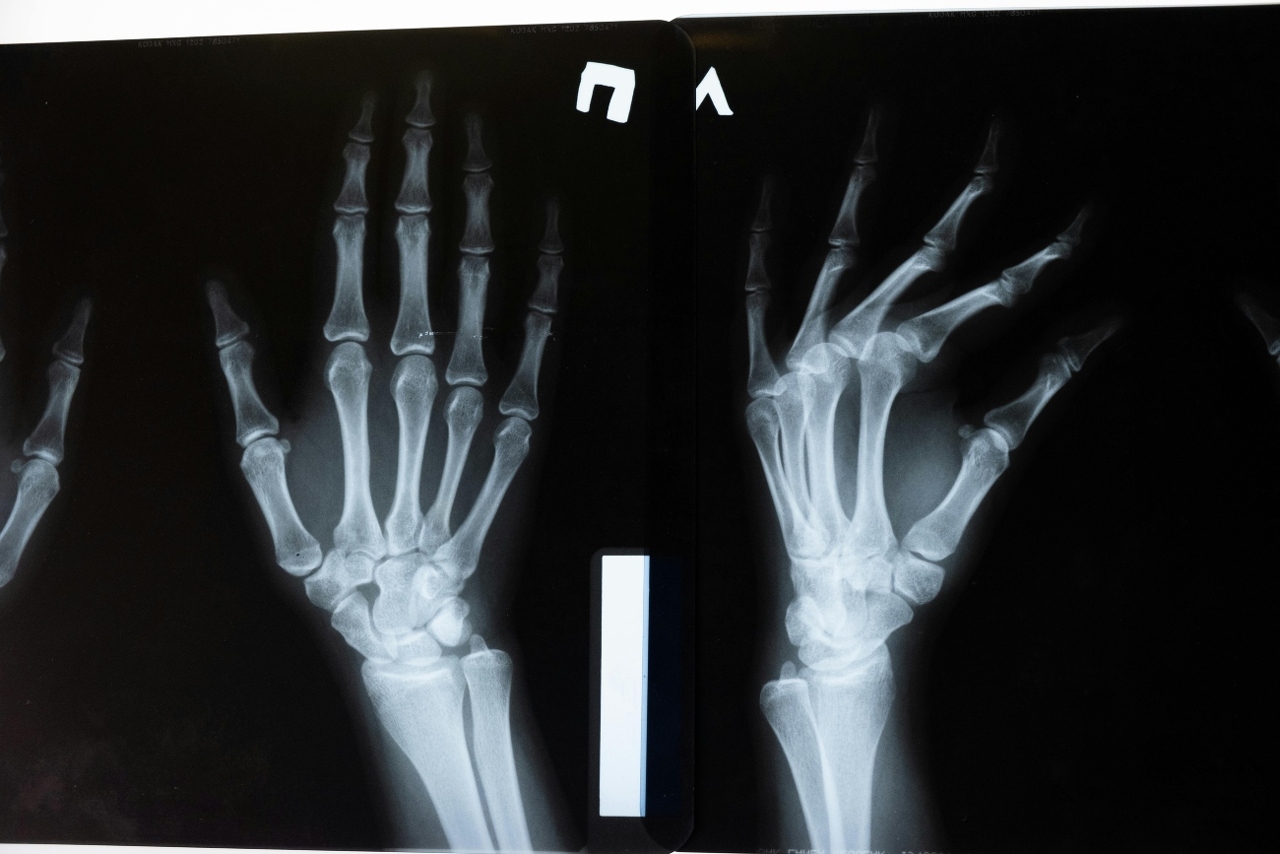

„Rendgenske snimke također ne pokazuju nikakve promjene koje bi se mogle povezati s ovom navikom.“

Kao jedan od najupečatljivijih primjera navodi se slučaj američkog liječnika koji je više od 60 godina svakodnevno pucketao zglobovima samo jedne ruke, kako bi dokazao majci da to nije štetno. Na kraju, pregledom obje ruke nije pronađen nijedan znak artritisa – ni na ruci koju je pucketao, ni na drugoj.